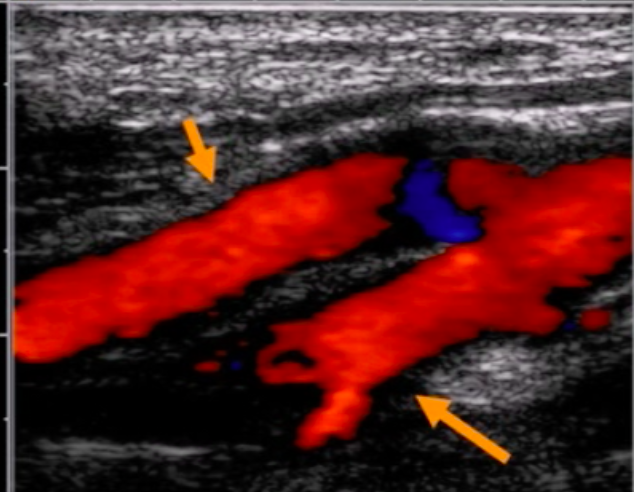

Carotid DUS imaging shown below. Diagnosis?

near-total ICA occlusion

note significant ICA plaque with low velocities distal to lesion (“falling off spencer-reid curve”)